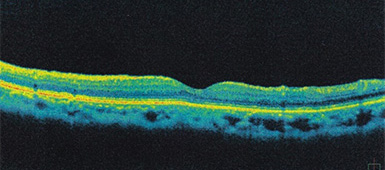

黄斑部が硝子体被膜に引っ張られ、穴が開いているのが分かります。

黄斑部の硝子体被膜が取り除かれ、円孔が綺麗に閉じていることが分かります。